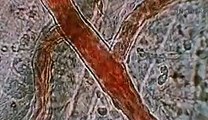

The average lifespan for Americans is 78.5 years. Over that time the human body goes on a remarkable journey. To stay alive the human body needs to reproduce, grow and adapt. But just how much skin is replaced? How much salvia is swallowed? and how fast do fingernails actually grow?